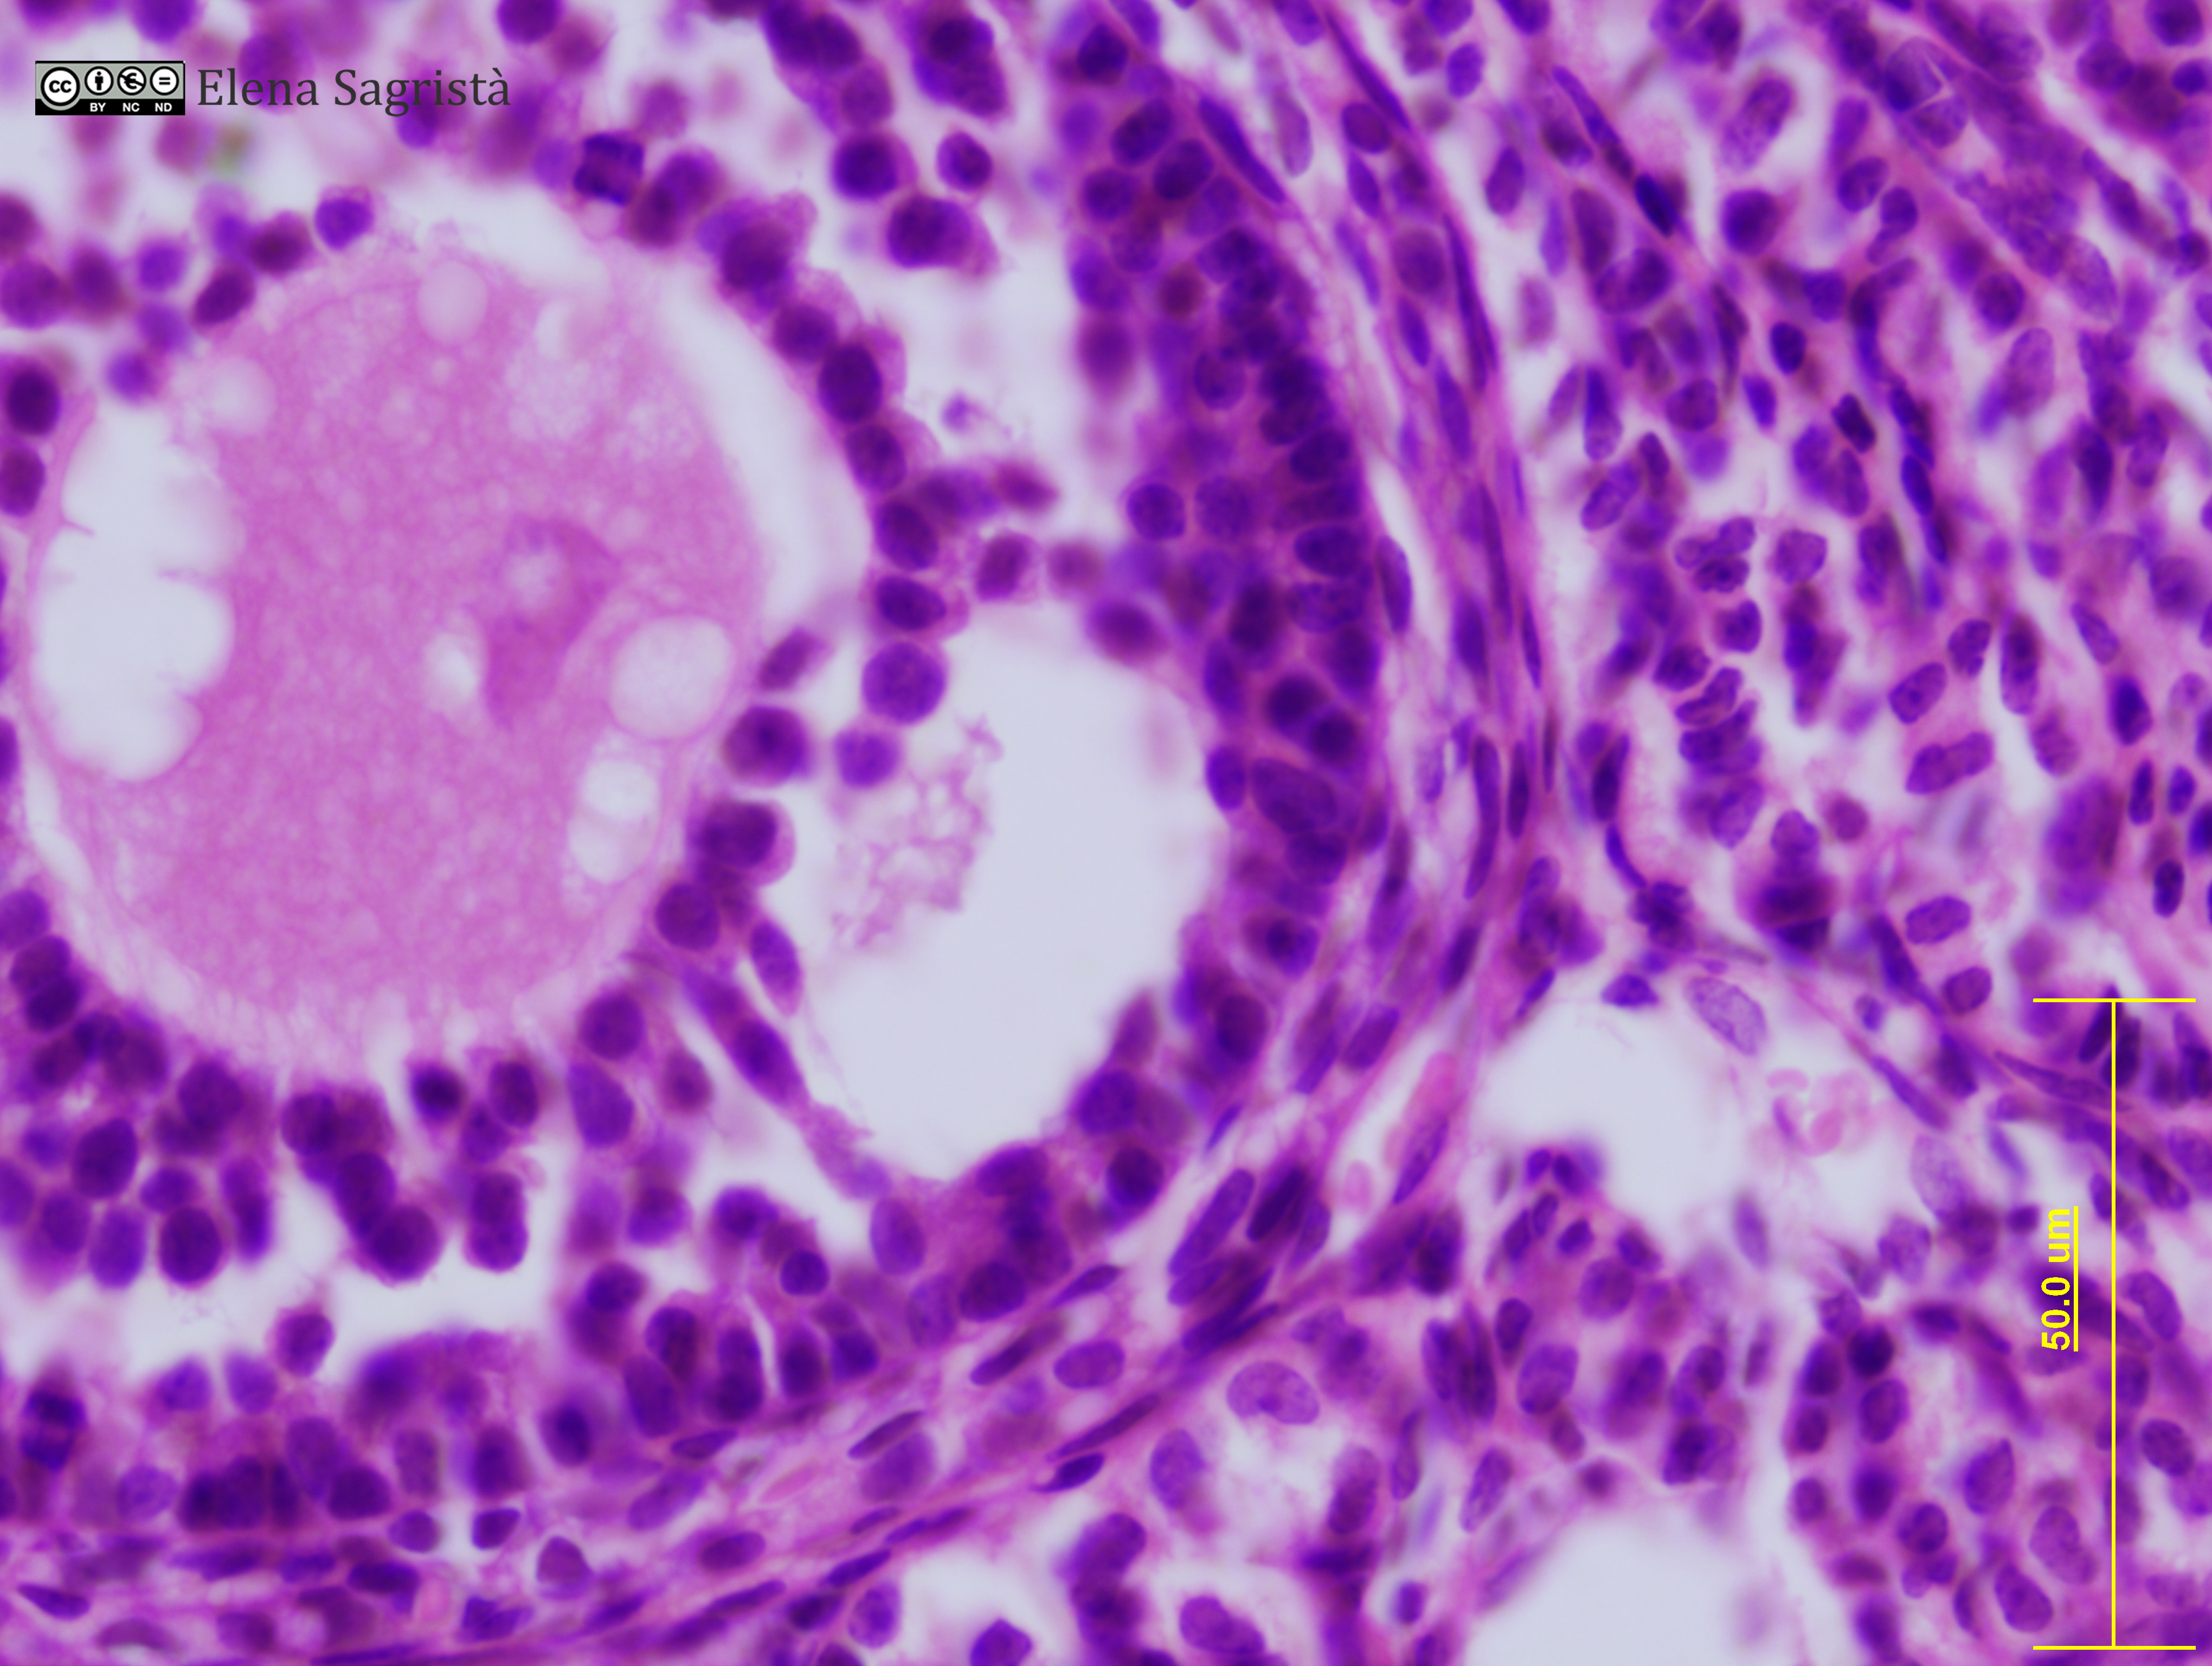

Imatges de preparacions histològiques d'Ovari i Aparell reproductor femení. Microscòpia òptica.